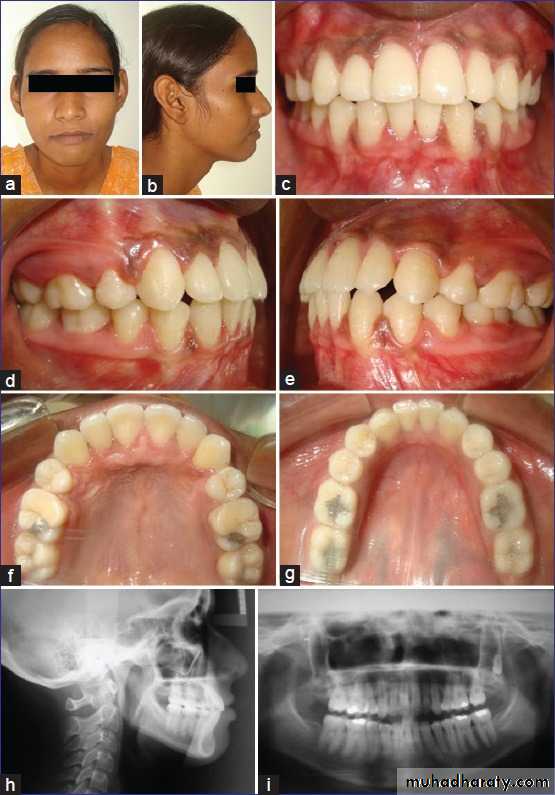

Surgical exposure :the path of eruption is not obstructed

impaction

Surgical exposure with orthodontic traction: the path of eruption is obstructed

Surgical exposure with orthodontic treatment (palatal approach )